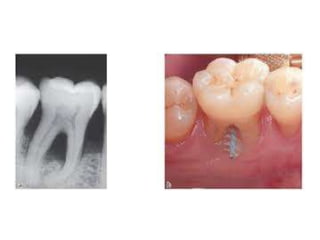

TRATAMENTO DAS LESÕES

ENDOPERIODONTAIS

Hemisseccção

DEL RIO, 1996